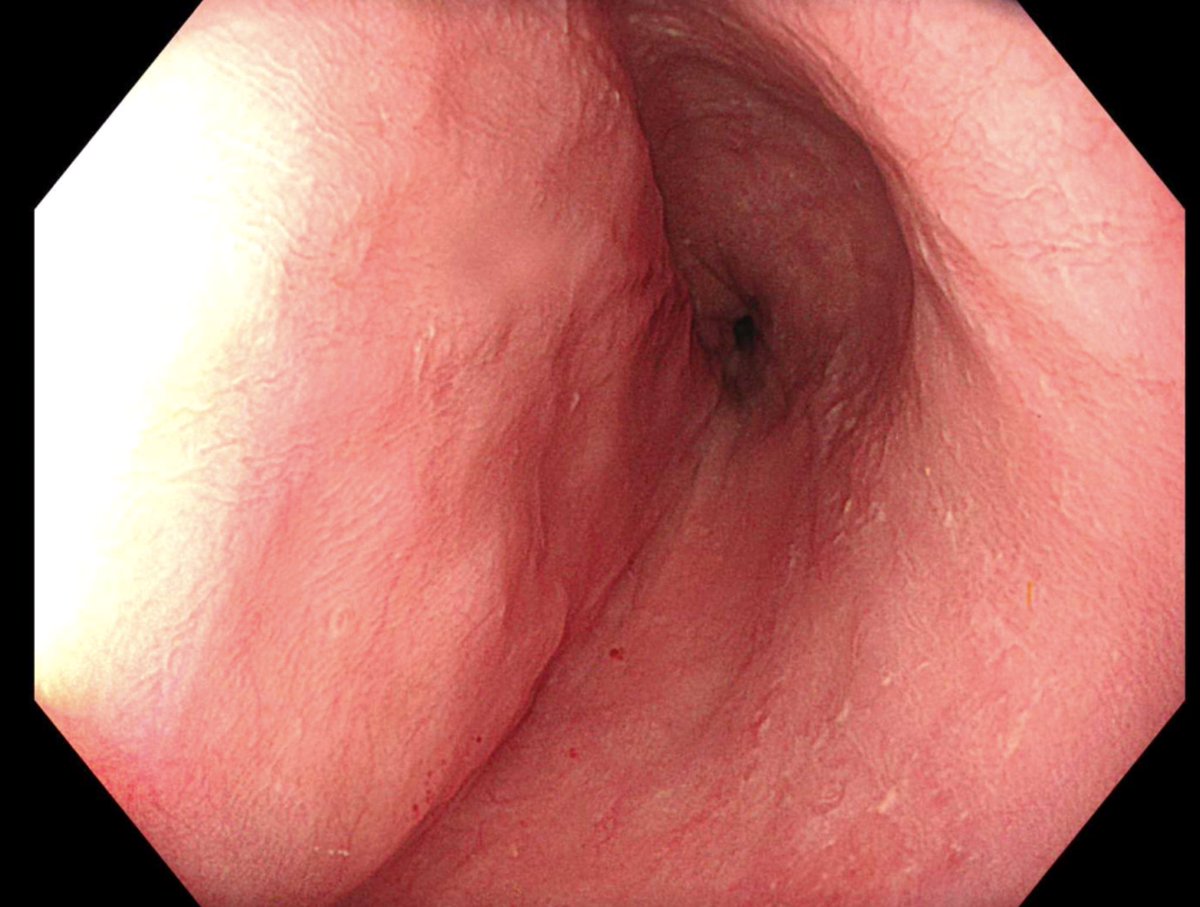

اما العملية الجراحية التي تجرى في حالات الاكاليزيا هي Heller myotomy و يقابلها من حيث الفعالية اجراء يجرى عن طريق المنظار و دون الحاجة لاجراء شق في البطن هي POEM و هي اختصار ل Peroral Endoscopic Myotomy و التي اثبتت فاعليتها في حل المشكلة بنسب عالية جدا.

هذه صور لاحدى الحالات التي اجريت في المستشفى الجامعي و التي بحمد الله تكللت بالنجاح بواسطة المنظار عن طريق اجراء فتحة صغيرة لا تتجاوز ٢ سم في المريء.